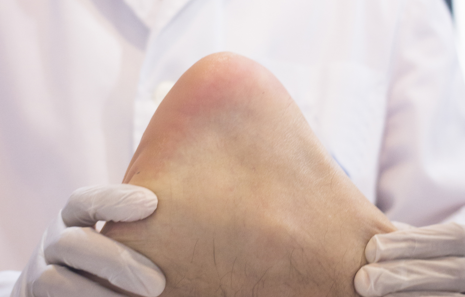

족저근막염은 발바닥 근막에 염증이 생겨 발생하는 통증을 말해요.

- 발뒤꿈치를 눌렀을 때 찌릿한 통증이 느껴지나요?

증상이 심하면 병원 치료가 필요할 수도 있어요.